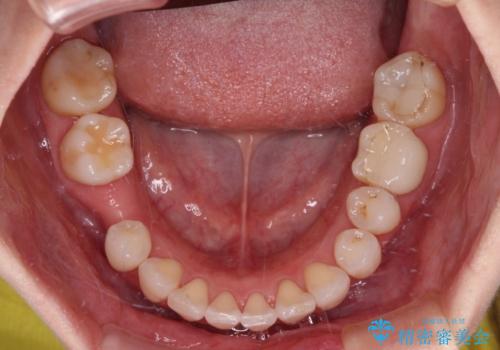

- 全体的なデコボコと、奥歯の欠損を放置した結果倒れ込んだ奥歯などを気にして来院された患者様です。

ワイヤー矯正の方が理想的な仕上がりとできる状態でしたが、上顎前歯にクラウンが装着されているため、インビザラインにて矯正治療を行うこととしました。

インビザラインのみで対応できないときにはワイヤー矯正を併用することとし、矯正治療後にはオールセラミッククラウンによる補綴治療を行うこととしました。